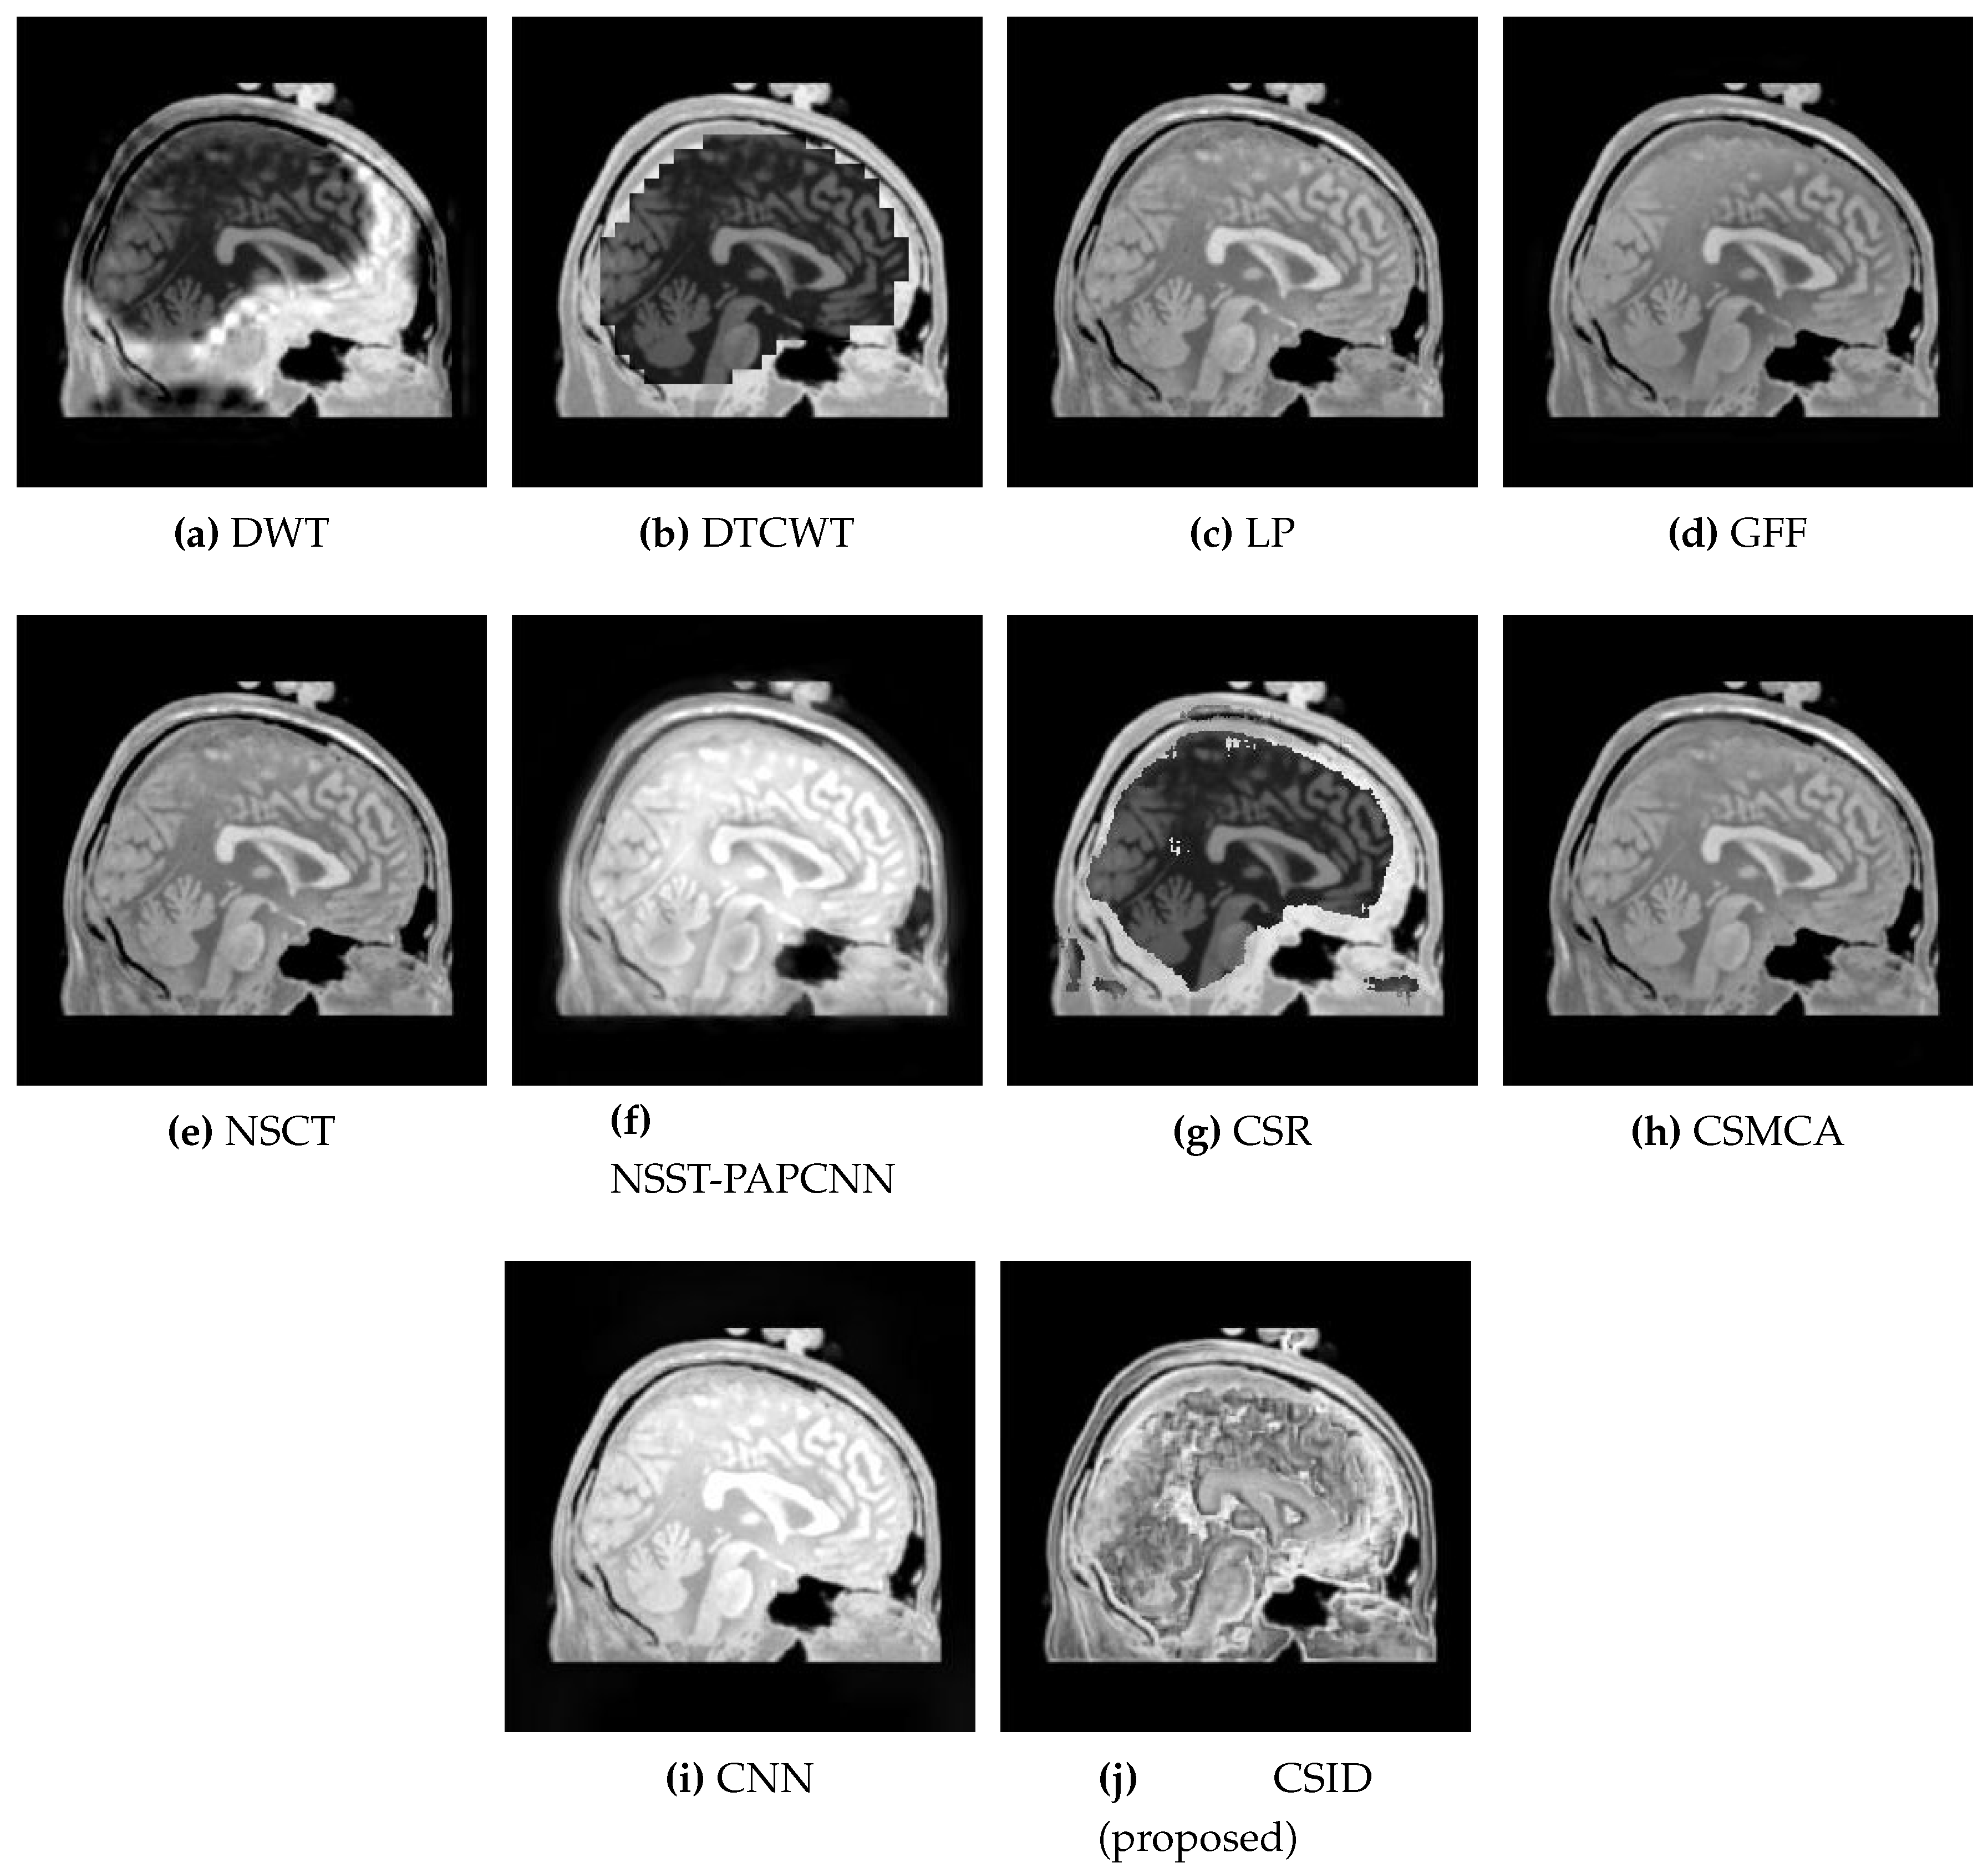

5.2.1. Qualitative Analysis of the Given Set of Algorithms for Multimodal Fusion